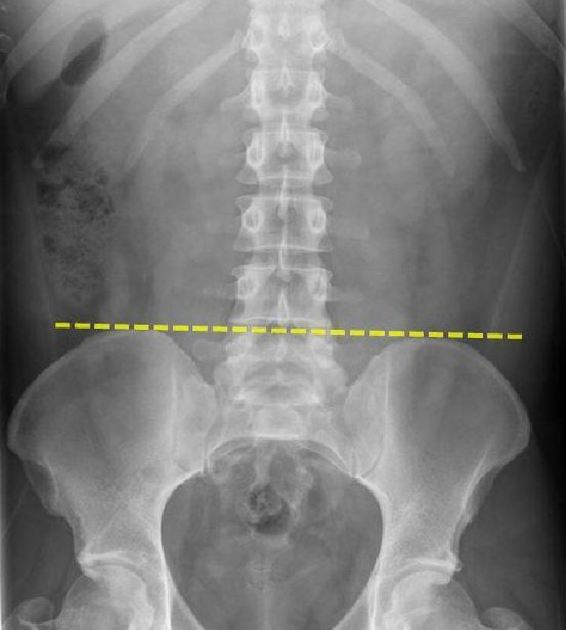

What is an imporant landmark to perform the LP

The spinous process of L4 vertebrae

aligns with the intercristal plane (a line drawn between iliac crests)

identifies the L4-5 intervertebral space, which is ideal site for performing LP